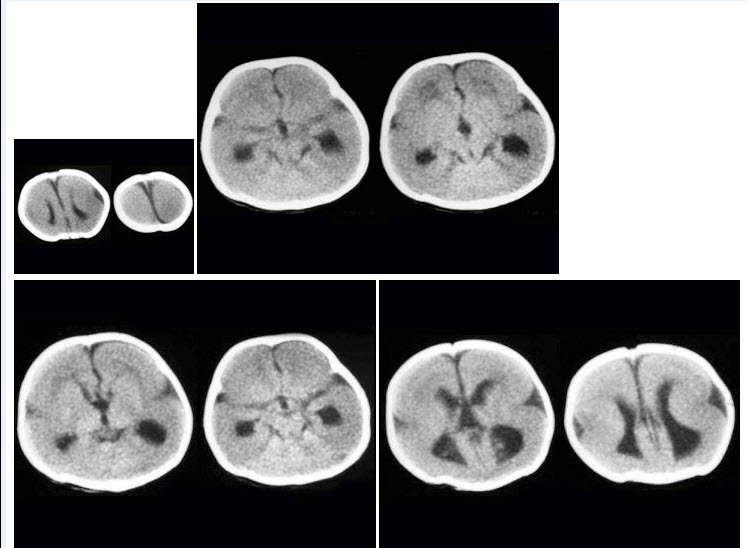

C.上鼓室

D.内耳道横嵴